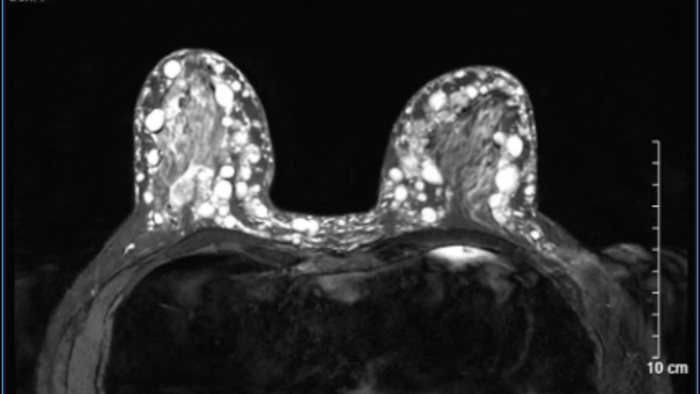

Hình chụp cho thấy các khối u cứng nổi rõ khiến bệnh nhân khó khăn trong sinh hoạt

Theo bác sĩ Hoàng Hồng, Trưởng khoa Phẫu thuật tạo hình thẩm mỹ, kết quả thăm khám, xét nghiệm và chụp chiếu cho thấy bệnh nhân bị u hạt silicon (siliconoma) hai bên ngực - biến chứng nặng nề của việc tiêm silicon lỏng.

Silicon đã thâm nhiễm toàn bộ tuyến vú, lan sang lớp mỡ dưới da, trung bì, thậm chí sát đến cân cơ ngực lớn. Đặc biệt, nhiều vùng tổn thương đã tiến triển nặng, silicon đẩy sát bề mặt da, đe dọa gây nhiễm trùng và hoại tử nếu chậm trễ can thiệp.